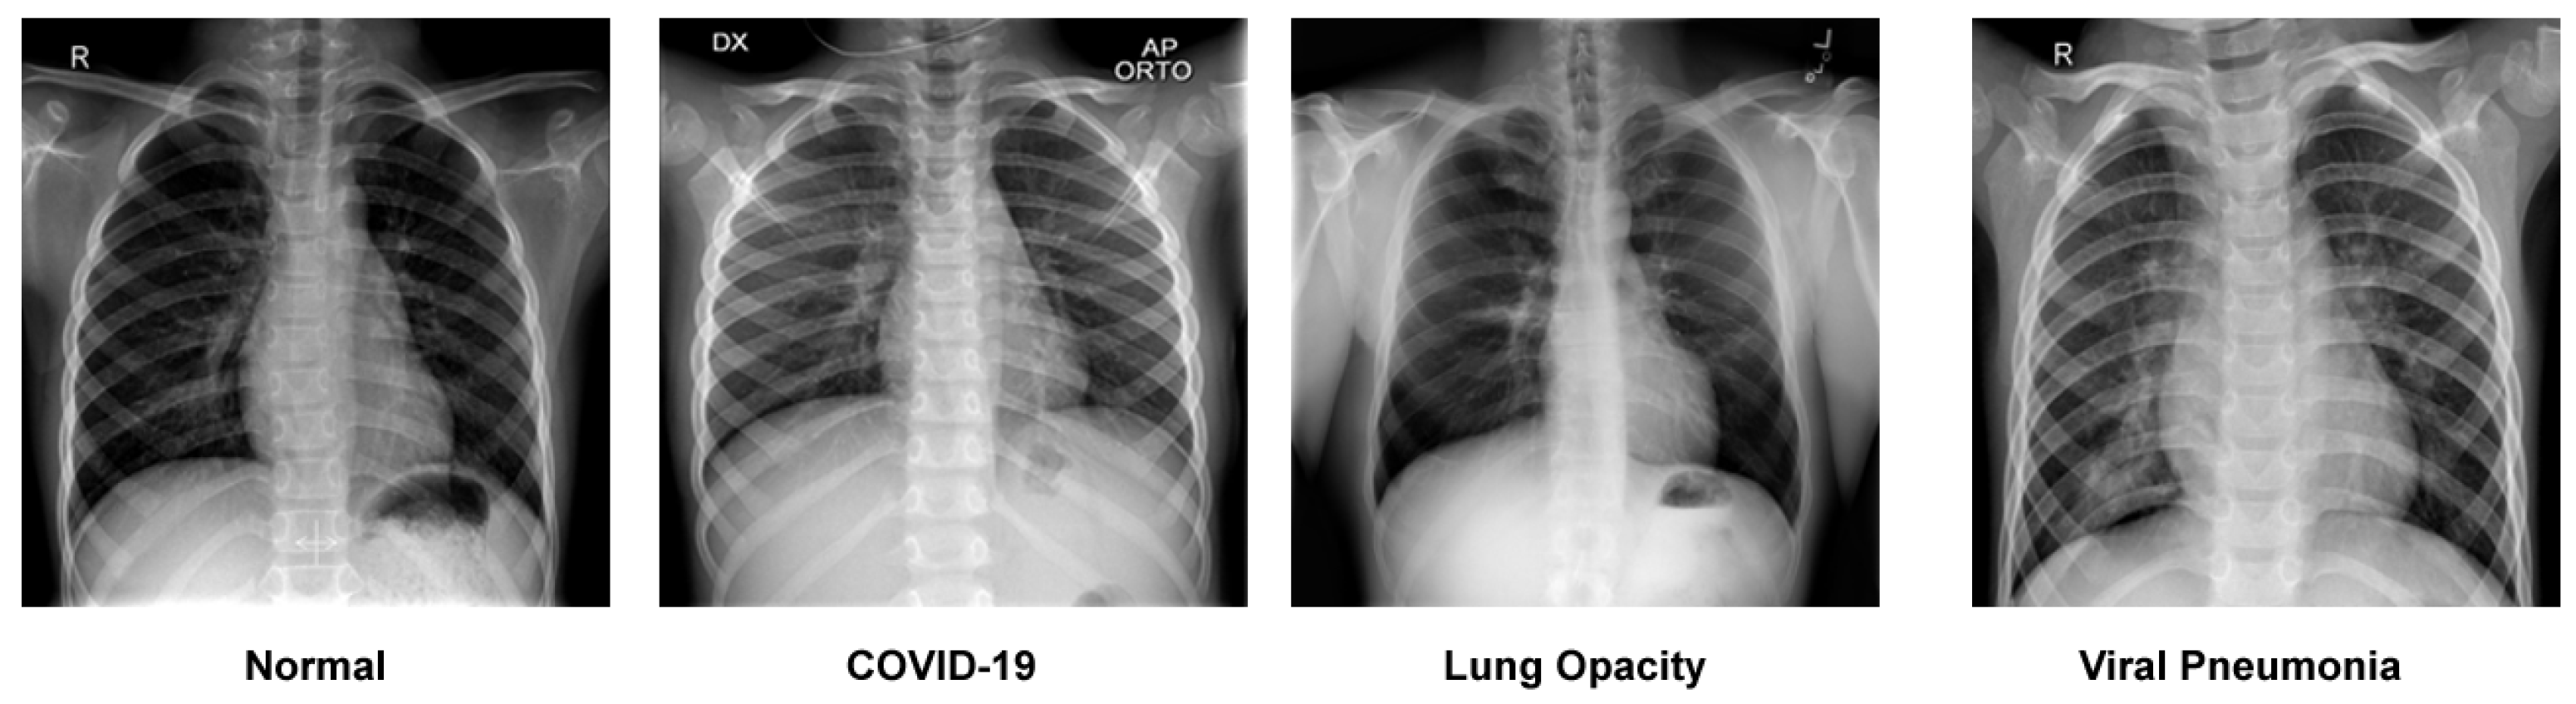

- Our design can classify four different categories of chest X-rays (COVID-19, normal, viral pneumonia and lung opacity). The accuracy of our approach is significantly higher than standard architecture and surpasses other state-of-the-art methods.

3.1. Dataset Description